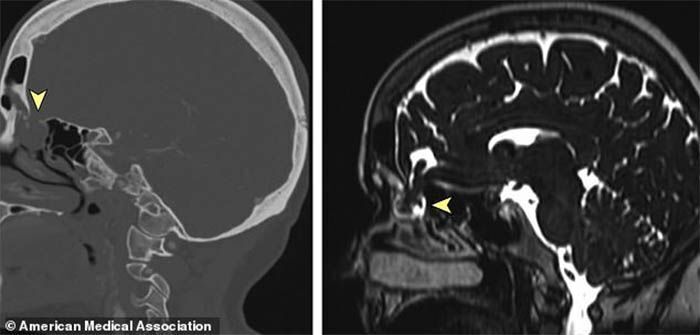

Cerebro Coronavirus Líquido cefalorraquídeo Los escáneres del cerebro de la mujer revelan una abertura sin diagnosticar en la base del cráneo. Después de que el hisopo "penetrara en el cerebro" comenzó a filtrar líquido cefalorraquídeo por la nariz

Una vez de vuelta al hospital, los médicos, capitaneados por el doctor Jarrett Walsh, le hicieron tomografías computarizadas de su cráneo, así como también fotografías de su pasaje nasofaríngeo. Así lo publicó dicha eminencia médica en un artículo en la revista especializada JAMA Otolaryngology-Head & Neck Surgery.  Dichas imágenes no dejaban lugar a la duda. Era notablemente visible un agujero en la base de su cráneo, el cual se abría en el mismo espacio donde había sido frotada con el hisopo para la prueba de coronavirus.